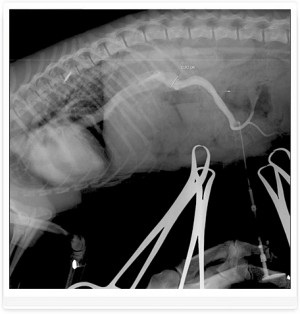

Foto 1. șunt ductul venos - o navă care leagă vena ombilicala la vena cava caudală a fătului

Foto 3. shunts portocaval - venei porte drenaj în vena cava caudală

Foto 4. shunts portocaval - venei porte drenaj în vena cava caudală

Diagnosticul EXEMPLU și tratamentul shunt. Câine rasa Yorkshire Terrier